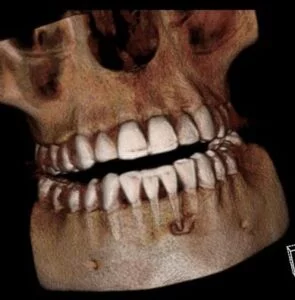

I wanted to share a unique case we’ve had with one of our patients.  This patient presented for a routine periodic exam. We hadn’t taken anterior PAs prior to this appointment.  However, upon seeing anterior PA’s, an apical radiolucency was noted on #24.

A CBCT was taken after a negative cold test indicated a necrotic tooth.  When the CBCT was taken, we could clearly see that the abscess had completely perforated the labial bone at the apex of #24 and was close to doing so on #25.

As we investigated more deeply, we identified another critical piece of information that would affect our treatment plan: a second canal on #24.